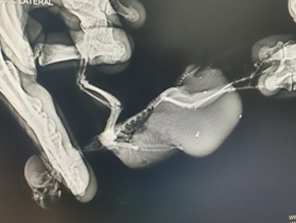

Асцит у самца волнистого попугайчика, обусловленный гиперплазией семенников

Асцит у самки волнистого попугайчика, вызванный поликистозом яичника и гиперплазией яйцевода